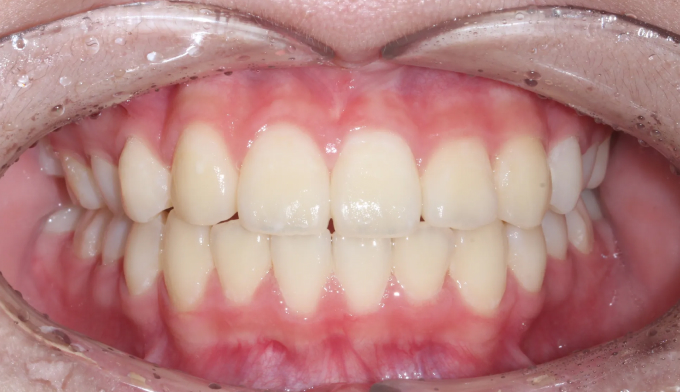

선천적으로 위 앞니 하나가 부족하여 치열이 틀어지게 된 경우입니다.(화살표 부위의 치아가 선천적으로 없습니다)

윗니와 아랫니와 치아 갯수가 맞지 않은 경우 교합이 틀어지게 되어 바른 얼굴을 갖지 못하게 되는 경우가 생깁니다. 올바른 교합의 형성은 성장기 어린이의 바른얼굴 형성에 도움을 줍니다.

틀어진 이들을 원래의 위치로 당겨서 위아래 중심선을 맞춰줍니다.

총 교정기간은 17개월 소요되었습니다.